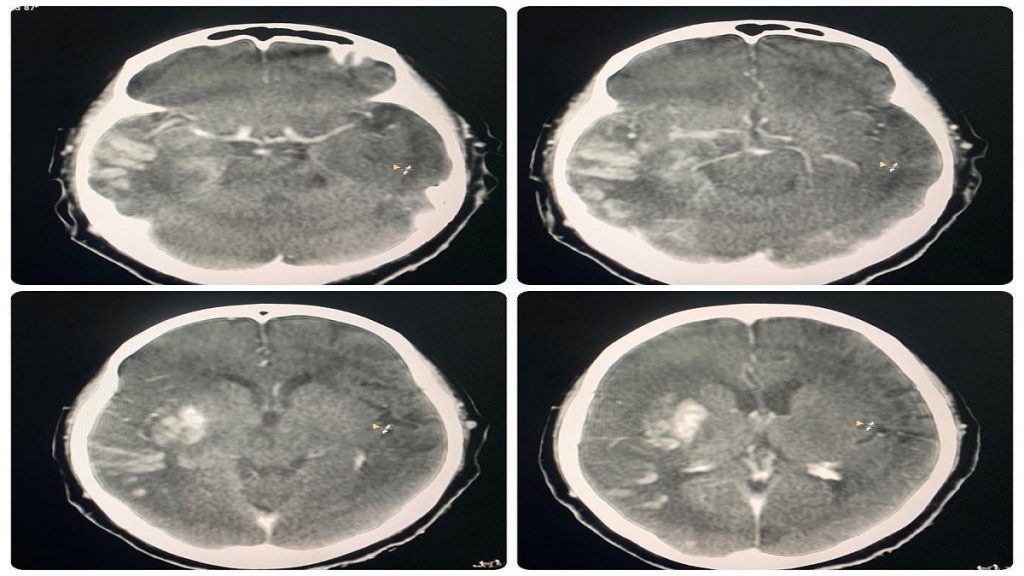

«Пациентка поступила с клинико-неврологической симптоматикой ишемического инсульта в бассейне правой средней мозговой артерии: левосторонний гемипарез, центральный парез лицевой мускулатуры слева, нарушение речи — дизартрия. Время начала заболевания 1 час. В экстренном порядке проведена операция — селективная церебральная ангиография, где выявлена картина острой окклюзии (тромбоз/тромбоэмболия) правой внутренней сонной артерии на уровне офтальмического сегмента»,- рассказывает заведующий отделением сосудистой нейрохирургии ГКБ №7 Алматы Рауан Кастей.

Как отметил специалист, тромб мог привести к тяжелым последствиям и даже к летальному исходу. Далее проведена рентгенэндоваскулярная механическая тромбаспирация тромба из правой внутренней сонной артерии с применением нововнедренного в больнице аспирационного катетера RED72, вместо ранее использовавшегося ACE62. По словам нейрохирурга, преимуществами нового катетера являются: увеличенный внутренний просвет, обеспечивающий наиболее высокую силу удаления тромба, улучшенное гидрофильное покрытие для плавного отслеживания и более дистального прохождения и в совокупности — достижение желаемого результата.

Операция прошла успешно, осложнений и рецидивов не было. Проведенная контрольная ангиограмма подтвердила полное восстановление кровообращения в бассейнах правой средней мозговой артерии и правой передней мозговой артерии.